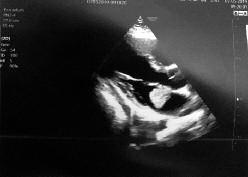

261 Riscontro ecocardiografico di mixoma atriale durante la valutazione dell’idoneità cardiologica ai fini del reclutamento in Forza Armata

E ch o c a r d i o g r a p h i c e v i d e n c e o f a t r i a l m y x o m a d u r i n g t h e assessment of cardiological suitability for recruitment into the Armed Force

Le visite di idoneità concorsuale, al pari di quelle arruolative all’epoca della leva, possono fungere da screening della popolazione giovane Il riscontro di anomalie congenite o acquisite, spesso misconosciute, può evitare conseguenze sanitarie gravi per il candidato, particolarmente in campo cardiologico